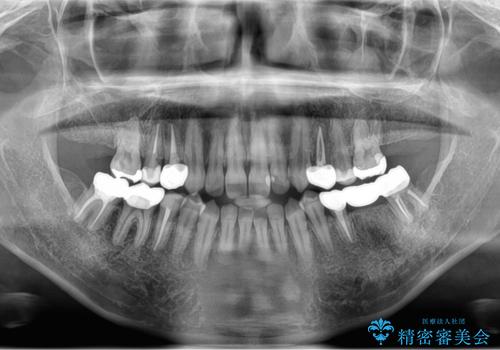

上顎の左右の奥歯が欠損(虫歯で失ったとのこと)していた部位はインプラント治療をお勧めしましたが、選択されませんでした。

その代わり、放置すると悪くなる部分は積極的に直し、高さがない部分はしっかり手術を行いかぶせました。

支える歯の本数が少ないうえに歯ぎしりもあるため、虫歯を治したとしても歯が割れるリスクがあります。

虫歯治療後にナイトガードを作成いただき、就寝時使用もらい予防を図っています。